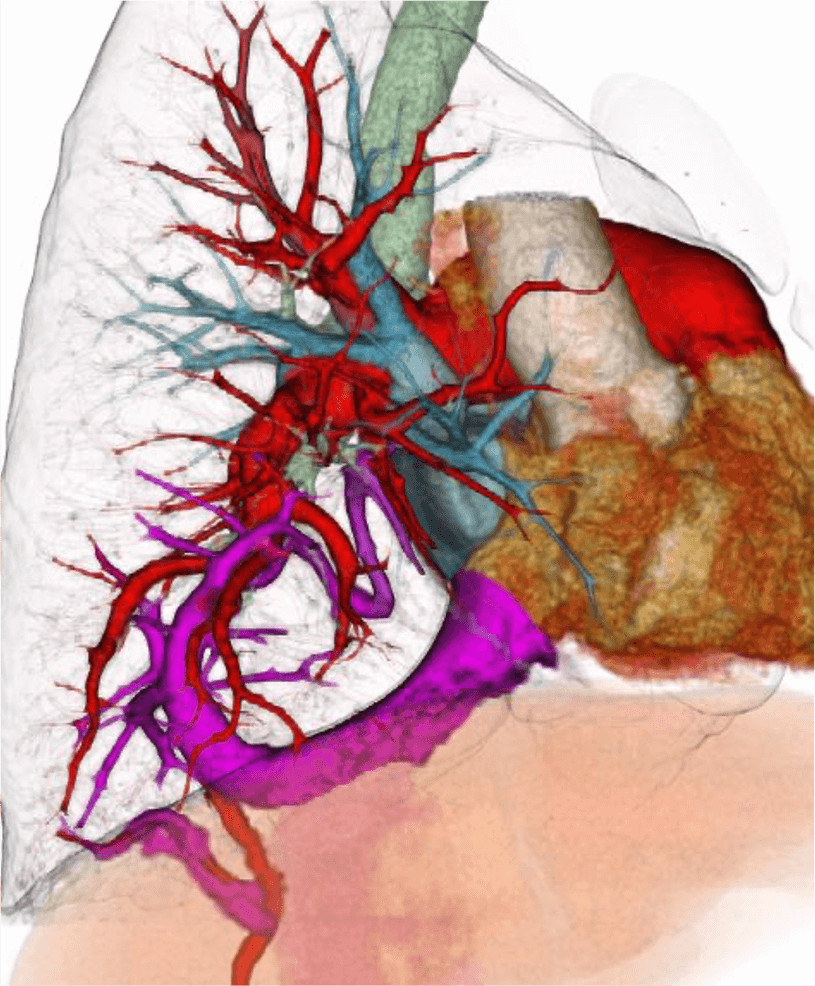

図3.3次元再構成VR像

左房に還流する通常の右下肺静脈は認められない。還流異常を生じた右下肺静脈は、右肺下葉を走行し、肝上部下大静脈に流入している(紫)。